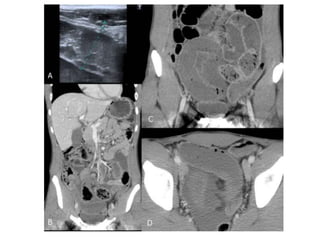

El estudio deTomografía por Computadora tiene una sensibilidad del 80 al 90% HALLAZGOS:  Dilatación proximal de intestino  Descompresión distal de intestino  Contraste intraluminal que no pasa más allá de la obstrucción  Intestino distal con poco gas

• La presenciade asa intestinal en forma de U o de C indica obstrucción de asa cerrada • Neumatosis intestinal, gas en la vena porta, opacidad mesentérica y captación deficiente del contraste intravenoso en la pared hace pensar en estrangulamiento